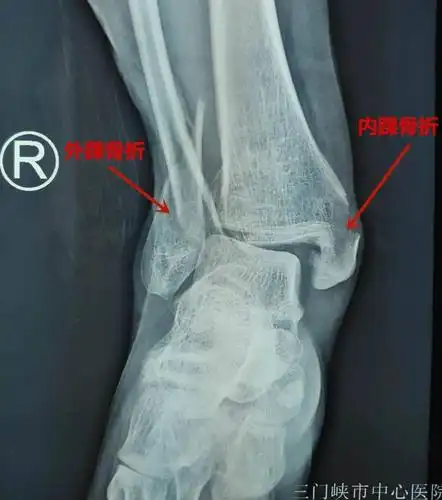

三踝骨折

三踝骨折一例讨论分型及治疗

三踝骨折伴脱位,欢迎拍砖! [病例帖]

一例三踝骨折请指教